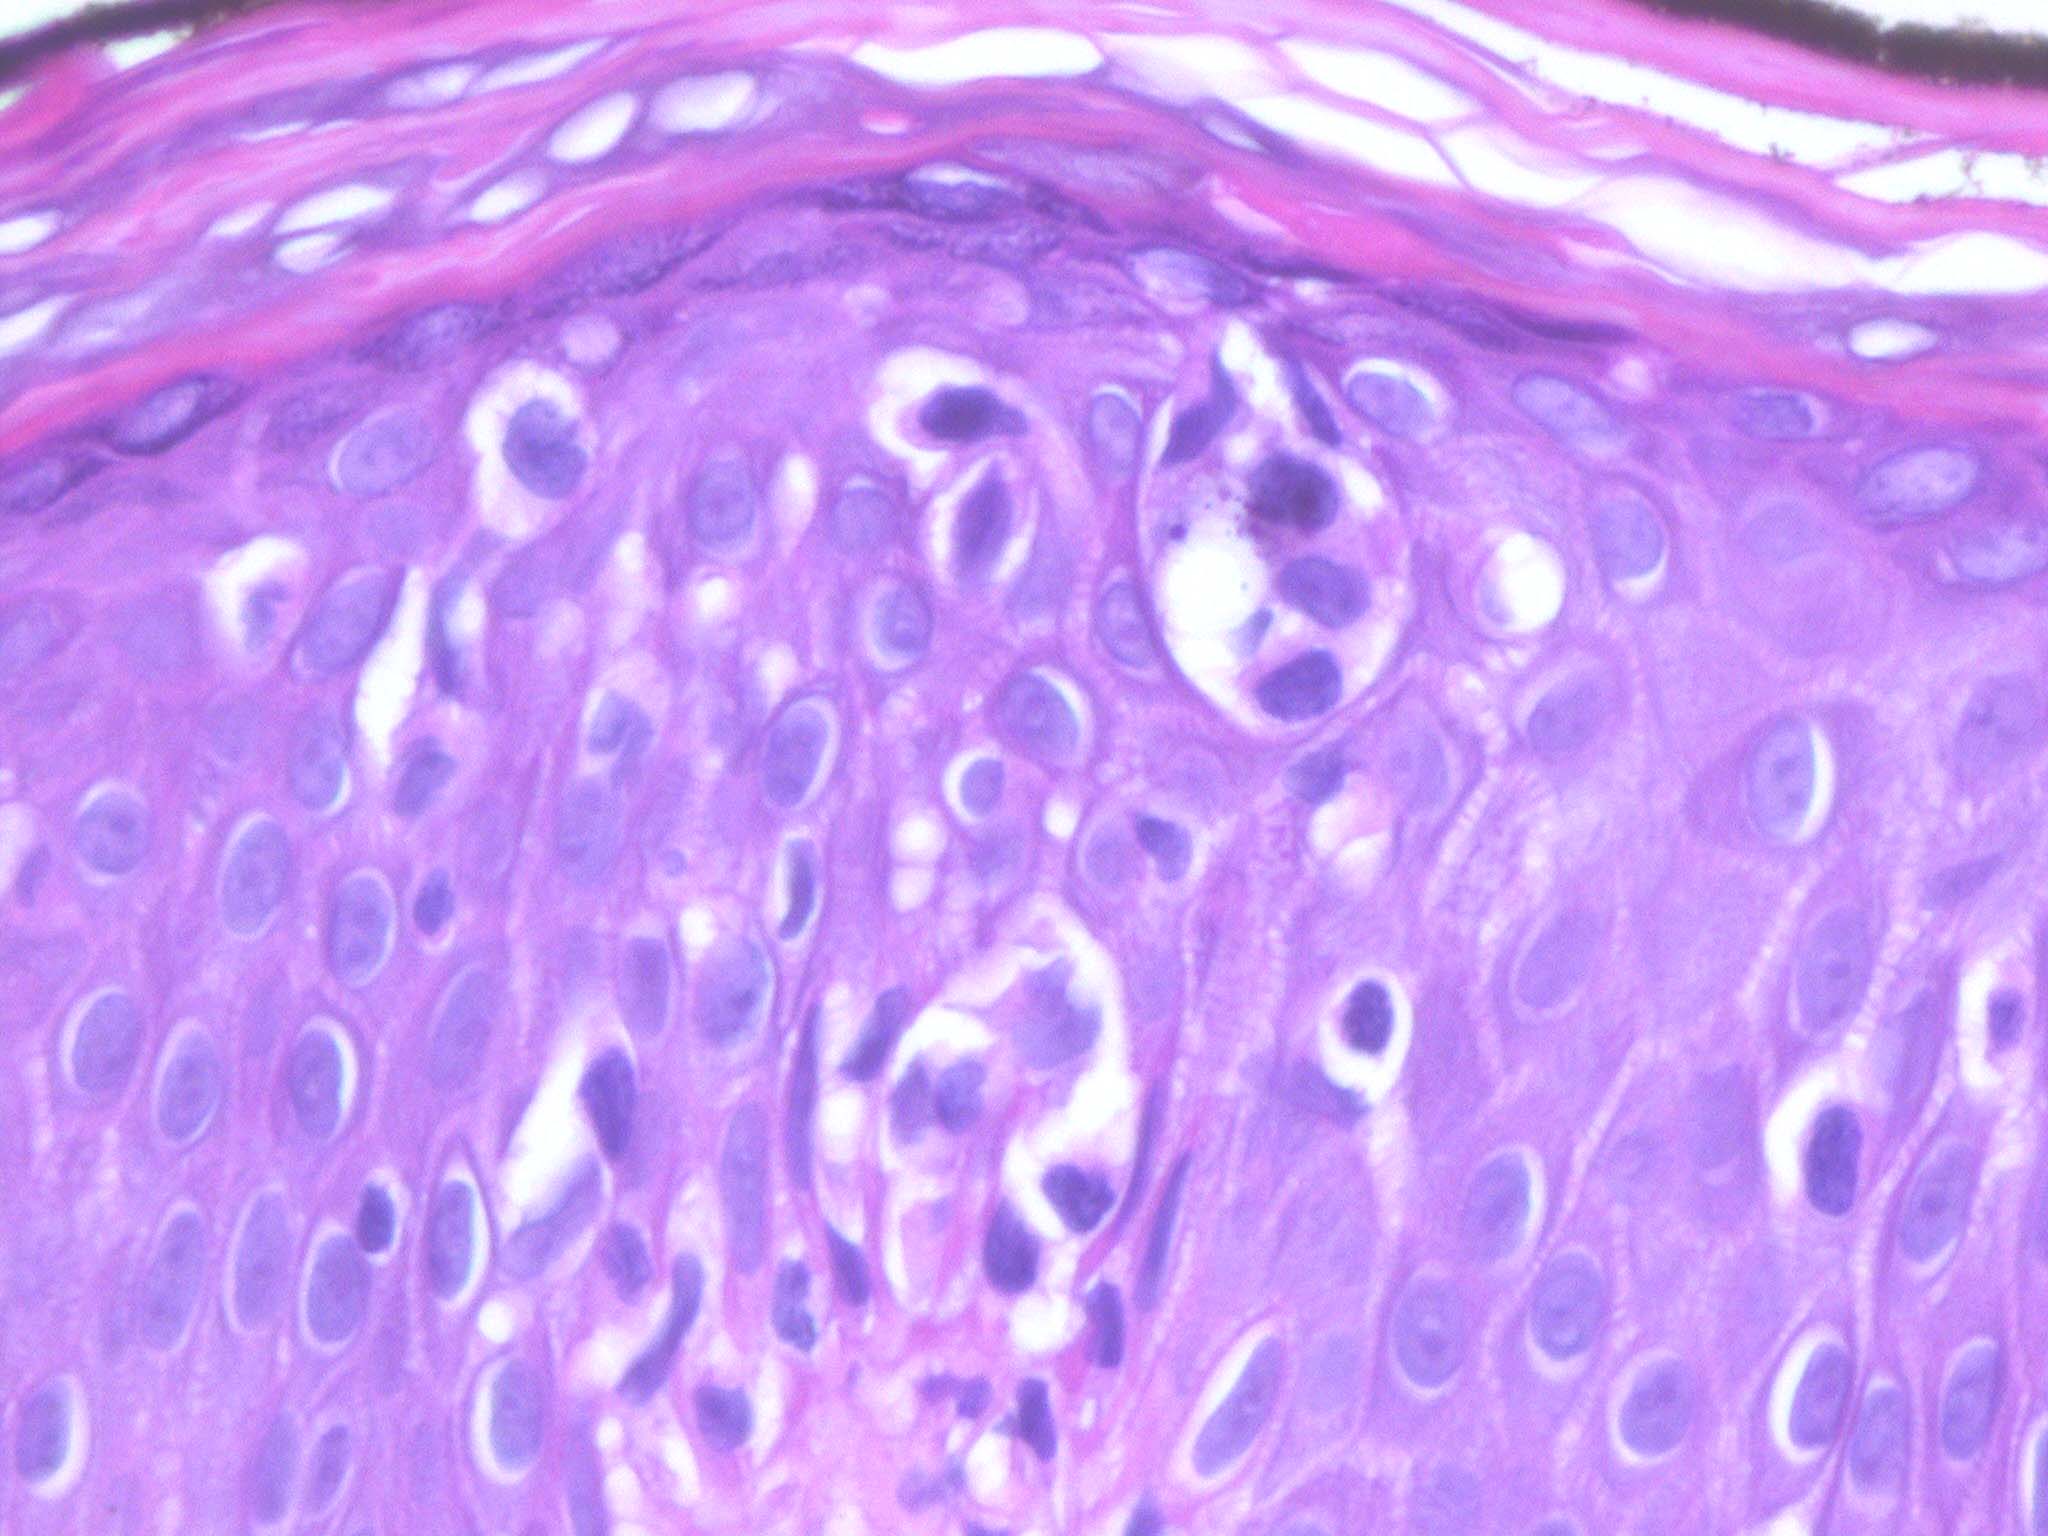

Mycosis Fongoïde =التفطر الكمئي